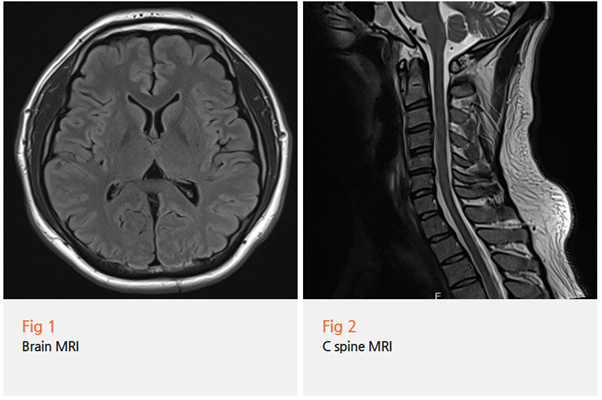

그래서 저는 주저하지 않고 뇌 MRI를 권했어요.

다행히 뇌 MRI 결과는 정상이었습니다.

뇌종양도, 뇌출혈도, 뇌경색도 없었어요.

하지만 여기서 끝이 아니었죠.

뇌가 정상이라는 건 좋은 소식이지만,

그렇다고 해서 두통 원인이 사라진 건 아니니까요.

저는 곧바로 목 MRI를 추가로 촬영했고,

결과를 보는 순간 '아하!' 하는 생각이 들었습니다.

상부 경추(목뼈 윗부분)에서 디스크가 살짝 튀어나와 있었고,

주변 근육들이 심하게 경직되어 있었거든요.